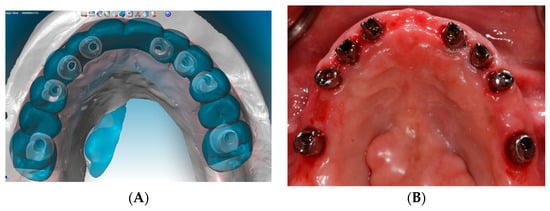

2.3. Surgical Phase: Virtual Planning of Implant Placement and Computer Guided Surgery

2.4. Restorative Phase: Second Strategic Extraction and Conversion of Provisional Prostheses with Integrated Digital Workflow